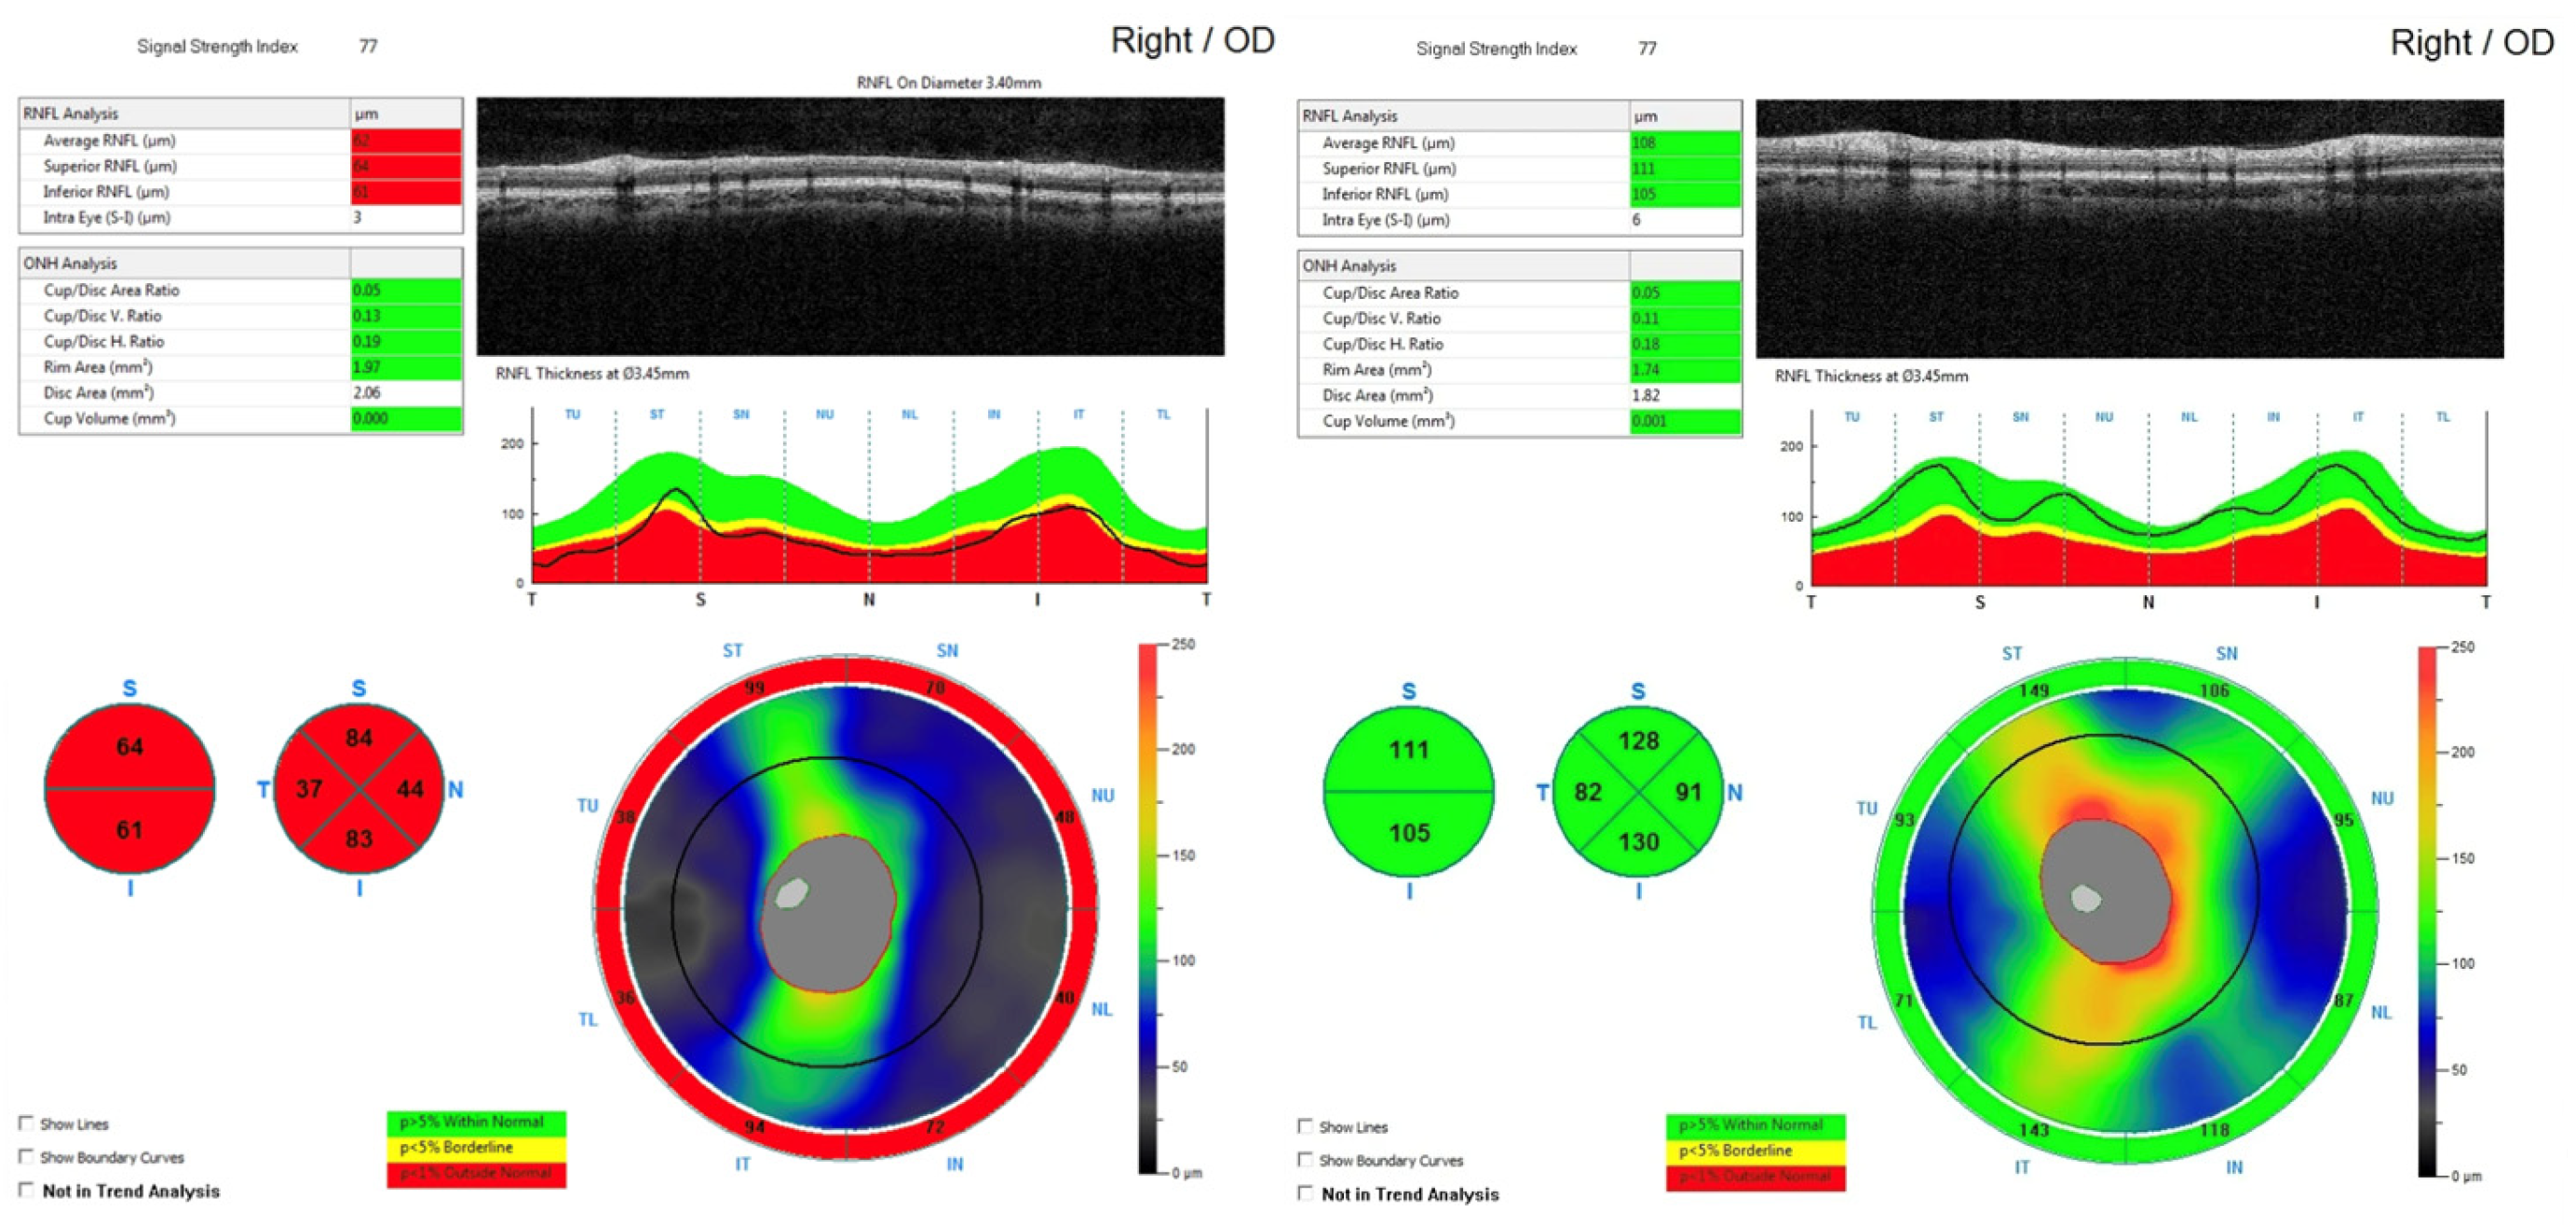

- Rakusiewicz-Krasnodębska, K.; Bogusz-Wójcik, A.; Moszczyńska, E.; Jaworski, M.; Kowalczyk, P.; Hautz, W. Evaluation of the Effect of Optic Nerve Compression by Craniopharyngioma on Retinal Nerve Fiber Layer Thickness in Pediatric Patients. Cancers 2025, 17, 2574. [Google Scholar] [CrossRef] [PubMed]

| Rakusiewicz-Krasnodębska et al. [64] (2025) | Children with CP | SD-OCT | RNFL | Significant RNFL thinning associated with optic nerve compression; RNFL thickness correlated with severity of visual impairment and reflected structural damage of the anterior visual pathway. |